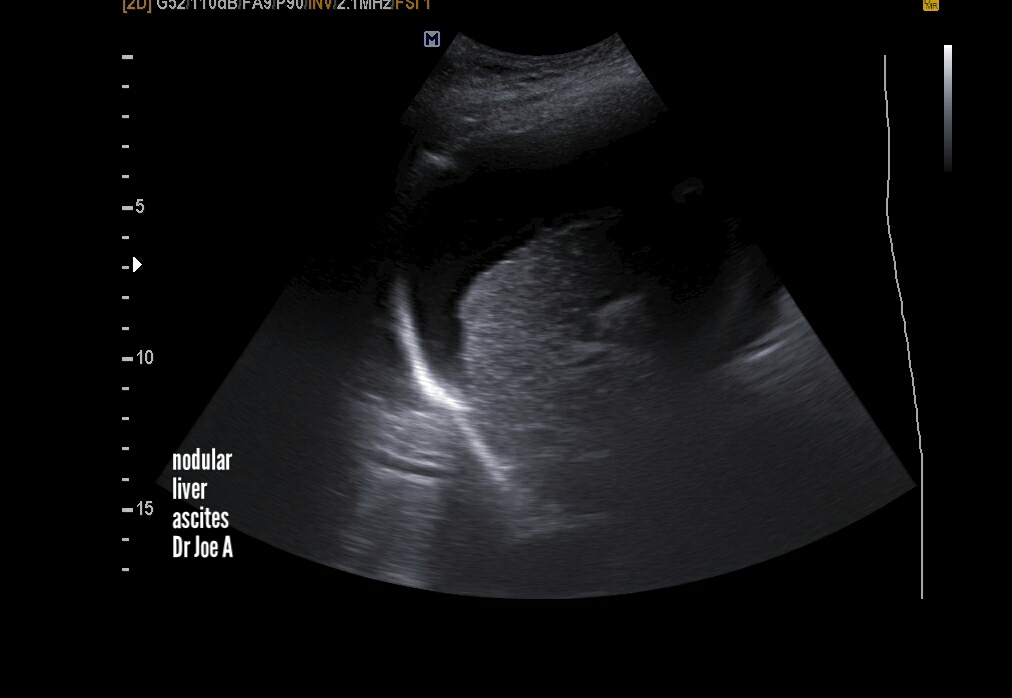

Cirrhosis-liver-ultrasound

End stage cirrhosis liver shows certain classic features seen in this case:

=Nodular shrunken liver

due to extensive fibrosis

= large ascites